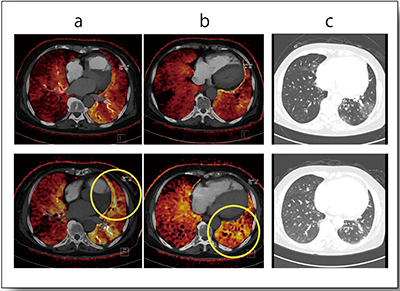

症例2はCTEPHである。CTAにLung PBVと肺血流シンチグラムをフュージョンした画像を比較したところ,灌流域のカラーマッピングはおおむね一致した(図3)。

図3 症例2:CTEPH(40歳代,女性)における

CTAとのフュージョン画像

a:CTA+Lung PBV

b:CTA+肺血流シンチグラム